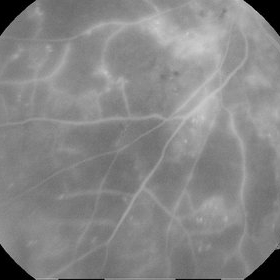

Neovascularization - RDP

A FAG image of a 84-year-old female. Late venous phase of the left eye. Hyperfloercent area in upper temporal quadrant represents NVE. Many hyperflorescent dots can be seen. Few hypoflorescent areas are deep retinal hemorrhages.

Photographer: Marko Lukic, University Eye Clinic Svjetlost

Imaging device: Zeis Visucam Lite 2

Condition/keywords: neovascularization (NV), neovascularization elsewhere (NVE)